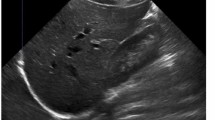

All CT images have a variable number of slices and were resampled to an axial resolution of 256 × 256 in order to reduce the computational load and amount of required GPU memory. CT images are by default stored as Hounsfield Units (HU), a standardized measurement of voxel density. For model input, the HU values were rescaled and clipped to [− 1, 1] using three different HU windows. A sample composite RGB image is shown in Fig. 2. Theoretically, a single HU window including all available information should be sufficient. However, it was empirically observed that using multiple windows led to better convergence, especially with mixed precision training.